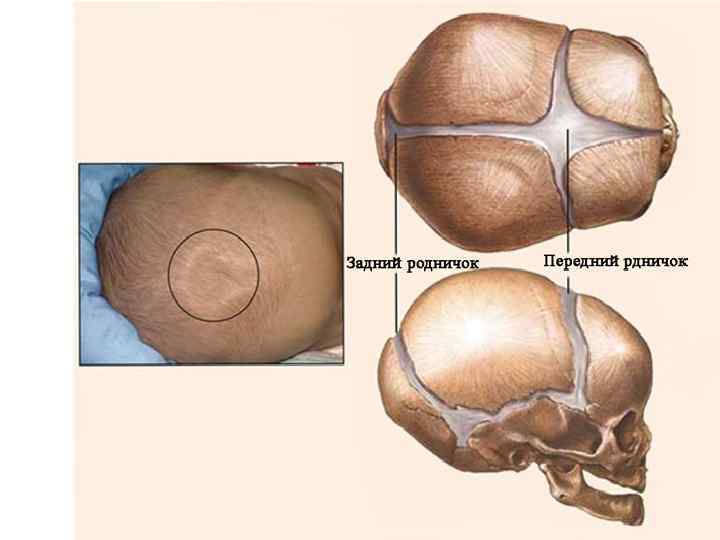

1) Передний родничок, fonticulus anterior , чаще имеет форму ромба, расположен у места схождения швов – сагиттального, венечного и метопического. Родничок сохраняется до 2 лет и к концу второго года окостеневает. 2) Задний родничок, fonticulus posterior , треугольной формы, располагается у места соединения сагиттального шва с ламбдовидным. Окостеневает в начале первого года жизни.

1) Передний родничок 2) Задний родничок 3) Клиновидный родничок 4) Сосцевидный родничок